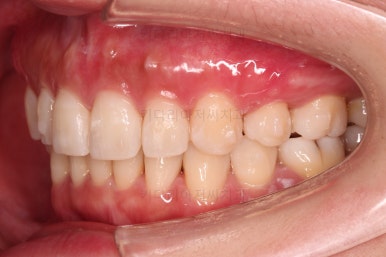

초진 시 입안의 모습인데요.

왜 그런지 비밀이 풀리는 것 같죠?

윗니는 한 쪽이 치아 2개가 결손이면서 유치가 하나 남아있고요.

아랫니는 한 쪽은 1개, 반대편은 2개 치아가 결손이었습니다.

도합 5개의 치아가 결손이었는데요.

결손 위치의 갯수가 위아래 좌우 다 달라서 중앙선이 맞을래야 맞을 수가 없는 상황이었죠.

결손치아 주위 치아들은 쓰러지고 비틀어져 있어서 장기적으로 좋지 못한 상황이었고요.

좀 더 디테일하게 윗니 작은 앞니 1개가 왜소치아라서 치아 크기도 맞지 않은 상황이었습니다.